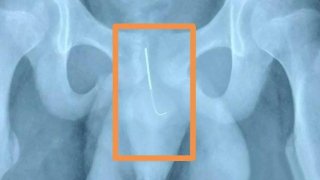

เด็กจีนยัดเข็มเข้าจู๋

สื่อต่างประเทศรายงานว่า "เด็กชาย วัย 13 ปี ในมณฑลเจียงซู ทางตะวันออก ของประเทศจีน ได้สอดเข็มเย็บผ้ายาว 9 เซนติเมตร เข้าไปในท่อปัสสาวะของเขา และ ทนเจ็บอยู่นาน 2 สัปดาห์ ก่อนที่เขาจะเดินทาง ไปยังโรงพยาบาล เพื่อผ่าตัดเอาเข็มออก..." เด็กชายรายนี้ได้นี้ถูกส่งตัวไปโรงพยาบาล ในเมืองหนานจิง มณฑลเจียงซู ทางตะวันออกของจีน เมื่อกลางเดือนที่ผ่านมา หลังจากที่เขาบ่นว่ารู้สึกเจ็บ และ มีเลือดออกระหว่างปัสสาวะ..... ดูเพิ่ม